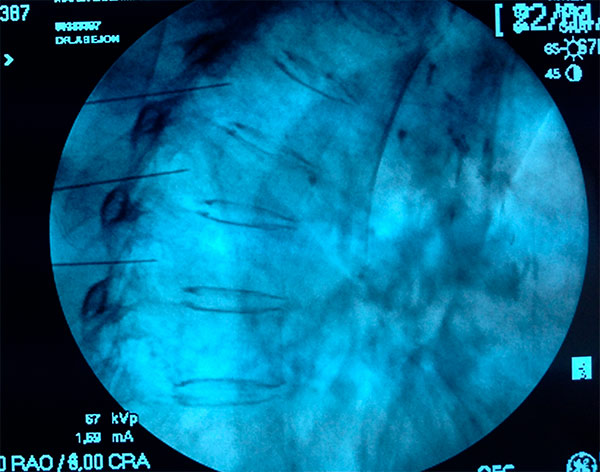

Con el paciente en decúbito prono y una almohada en la parte superior del abdomen se coloca el arco de fluoroscopia en posición AP para visualizar los cuerpos vertebrales T11 y T12 y las costillas adyacentes. Se gira a una posición oblicua (15-30º) para visualizar el target que es la unión condrocostal, de T11 y T12. Se infiltran los planos con anestésico local y se introduce en visión túnel un Abocath nº 16 por el que se introduce una aguja de radiofrecuencia curva de punta roma calibre 20 y de 15cm y se va avanzando lo más próximo posible al cuerpo vertebral. Se coloca el el arco de fluoroscopia en posición lateral hasta que la aguja este entre los dos tercios posteriores y el tercio anterior del cuerpo vertebral. Se cambia el el arco de fluoroscopia a posición AP quedando la aguja en el borde lateral del cuerpo vertebral y se inyecta contraste que debe difundir craneocaudalmente. Se inyecta 5ml de contraste para comprobar la situación correcta de la aguja y descartar localización intravascular.